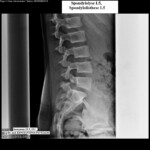

Ἡ διεθνὴς ταξινόμηση τῶν σταδίων τῆς σπονδυλολισθήσεως ἀκολουθεῖ τὸν ὑποδειχθέντα ὑπὸ τοῦ Meyerding κανόνα, σύμφωνα μὲ τὸν ὁποῖο τὸ μῆκος τῆς ὀλισθήσεως ἑνὸς σπονδύλου εἶναι συνάρτηση τοῦ μήκους τῆς βάσεως τοῦ ὑποκειμένου σπονδυλικοῦ σώματος. Ἡ διάγνωση ἢ ἡ ὑποψία μιᾶς σπονδυλολύσεως καὶ κατὰ τὶς περιστάσεις τῆς σπονδυλολισθήσεως τίθεται μὲ μία πλαγία ἀκτινογραφία ΟΜΣΣ καὶ μὲ ἐπικέντρωση στὸ ὕψος Ο4-Ο5-Ῑ1. Ὀριστικὴ ἐπιβεβαίωση δίδεται διὰ τῆς διενεργείας λοξῆς (45ο) ἀκτινογραφίας, ὅπου ἡ ἀπεικονιζόμενη σπονδυλόλυση περιγράφεται συχνὰ μὲ τὸν ἀποδοθέντα ὑπὸ τῶν παλιῶν ἀκτινολόγων ὑπέροχο ὅσον καὶ γλαφυρὸ ἀκτινολογικὸ ὅρο: «ἡ φιγούρα τοῦ σκύλου μὲ τὸ κολλάρο» Τὸ κολλάρο τοῦ σκύλου εἶναι ἡ διαυγαστικὴ γραμμὴ τοῦ ρωγμώδους κατάγματος τοῦ σπονδυλικοῦ τόξου!! (Οἱ εἰκ. 10,11,12 καὶ 13) ἀκριβῶς παρουσιάζουν τὴν 4ετῆ πορεία ἑνὸς κοριτσιοῦ , ποὺ σὲ ἠλικία 10 ἐτῶν, ὑπέστη σπονδυλόλυση καὶ σπονδυλολίσθηση τοῦ Ο5 ἐπὶ τοῦ Ι1 κατὰ τὴν διάρκεια ἀσκήσεως μοντέρνου χοροῦ. Χαρακτηριστικὴ εἶναι ἡ ὕπαρξη τοῦ ἀκτινολογικοῦ κριτηρίου «τῆς φιγούρας τοῦ σκύλου μὲ τὸ κολλάρο»!!) Ἐὰν τὰ εὑρήματα στὶς ἀκτινογραφίες δὲν εἶναι σαφῆ, ἐπιβάλλεται περαιτέρω ἔλεγχος μὲ μαγνητικὴ τομογραφία.

Σημ.: οἱ εἰκόνες 10, 11, 12, 13 καὶ 14 προέρχονται ἀπὸ τὸ ὑλικὸ ἀρχείου τοῦ ἐργαστηρίου μου.